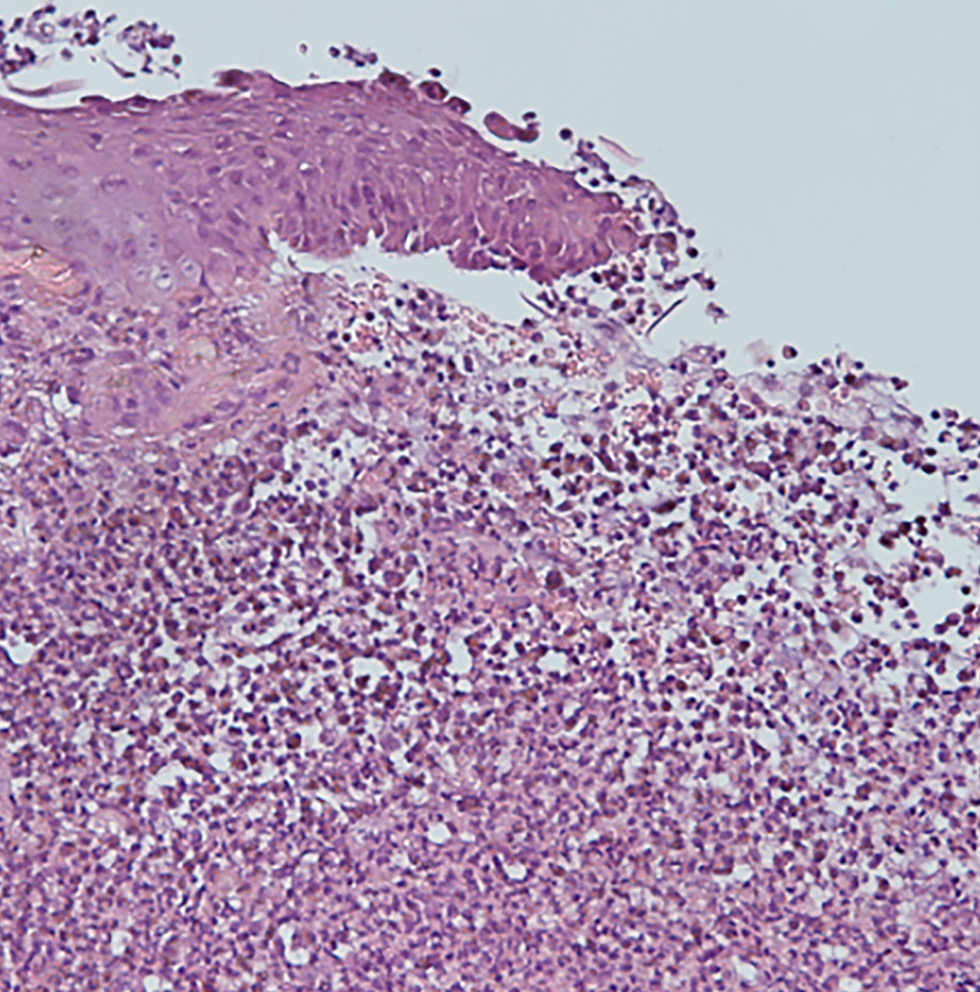

По данным гистологического исследования биоптата с краевой зоны язвы в эпидермисе определяются участок расщепления с формированием внутриэпидермального пузыря; участки отсутствия эпидермиса, покрытые гнойно-некротическим детритом; обильные поля густой нейтрофильной инфильтрации дермы с признаками лейкоцитокластического васкулита; очаги некрозов дермы (рис. 2).

Рис. 2. Тот же пациент. Гистологическая картина: смешанный воспалительный инфильтрат с преобладанием нейтрофилов и признаками лейкоцитокластического васкулита. Окраска гематоксилином и эозином, ×200. / Fig. 2. The same patient. Histologic image: mixed inflammatory infiltrate with a predominance of neutrophils and signs of leukocytoclastic vasculitis. Hematoxylin and eosinstaining, ×200.